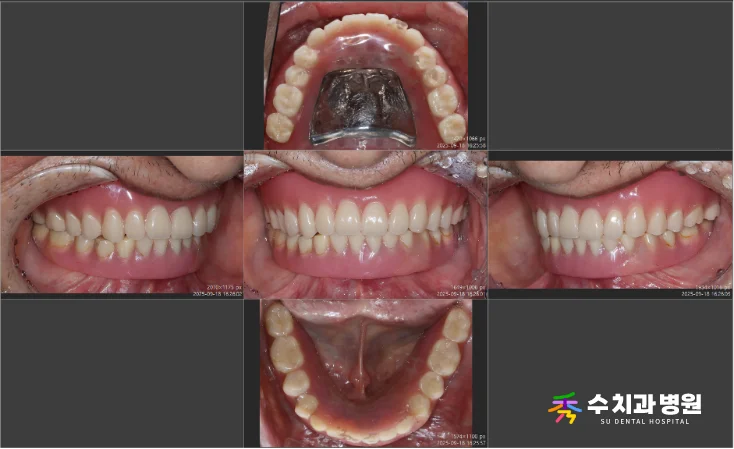

⚖️ 치료 전후 비교

[📸 치료 전후 비교 사진] (촬영일: 전 2025년 4월 / 후 2025년 9월)